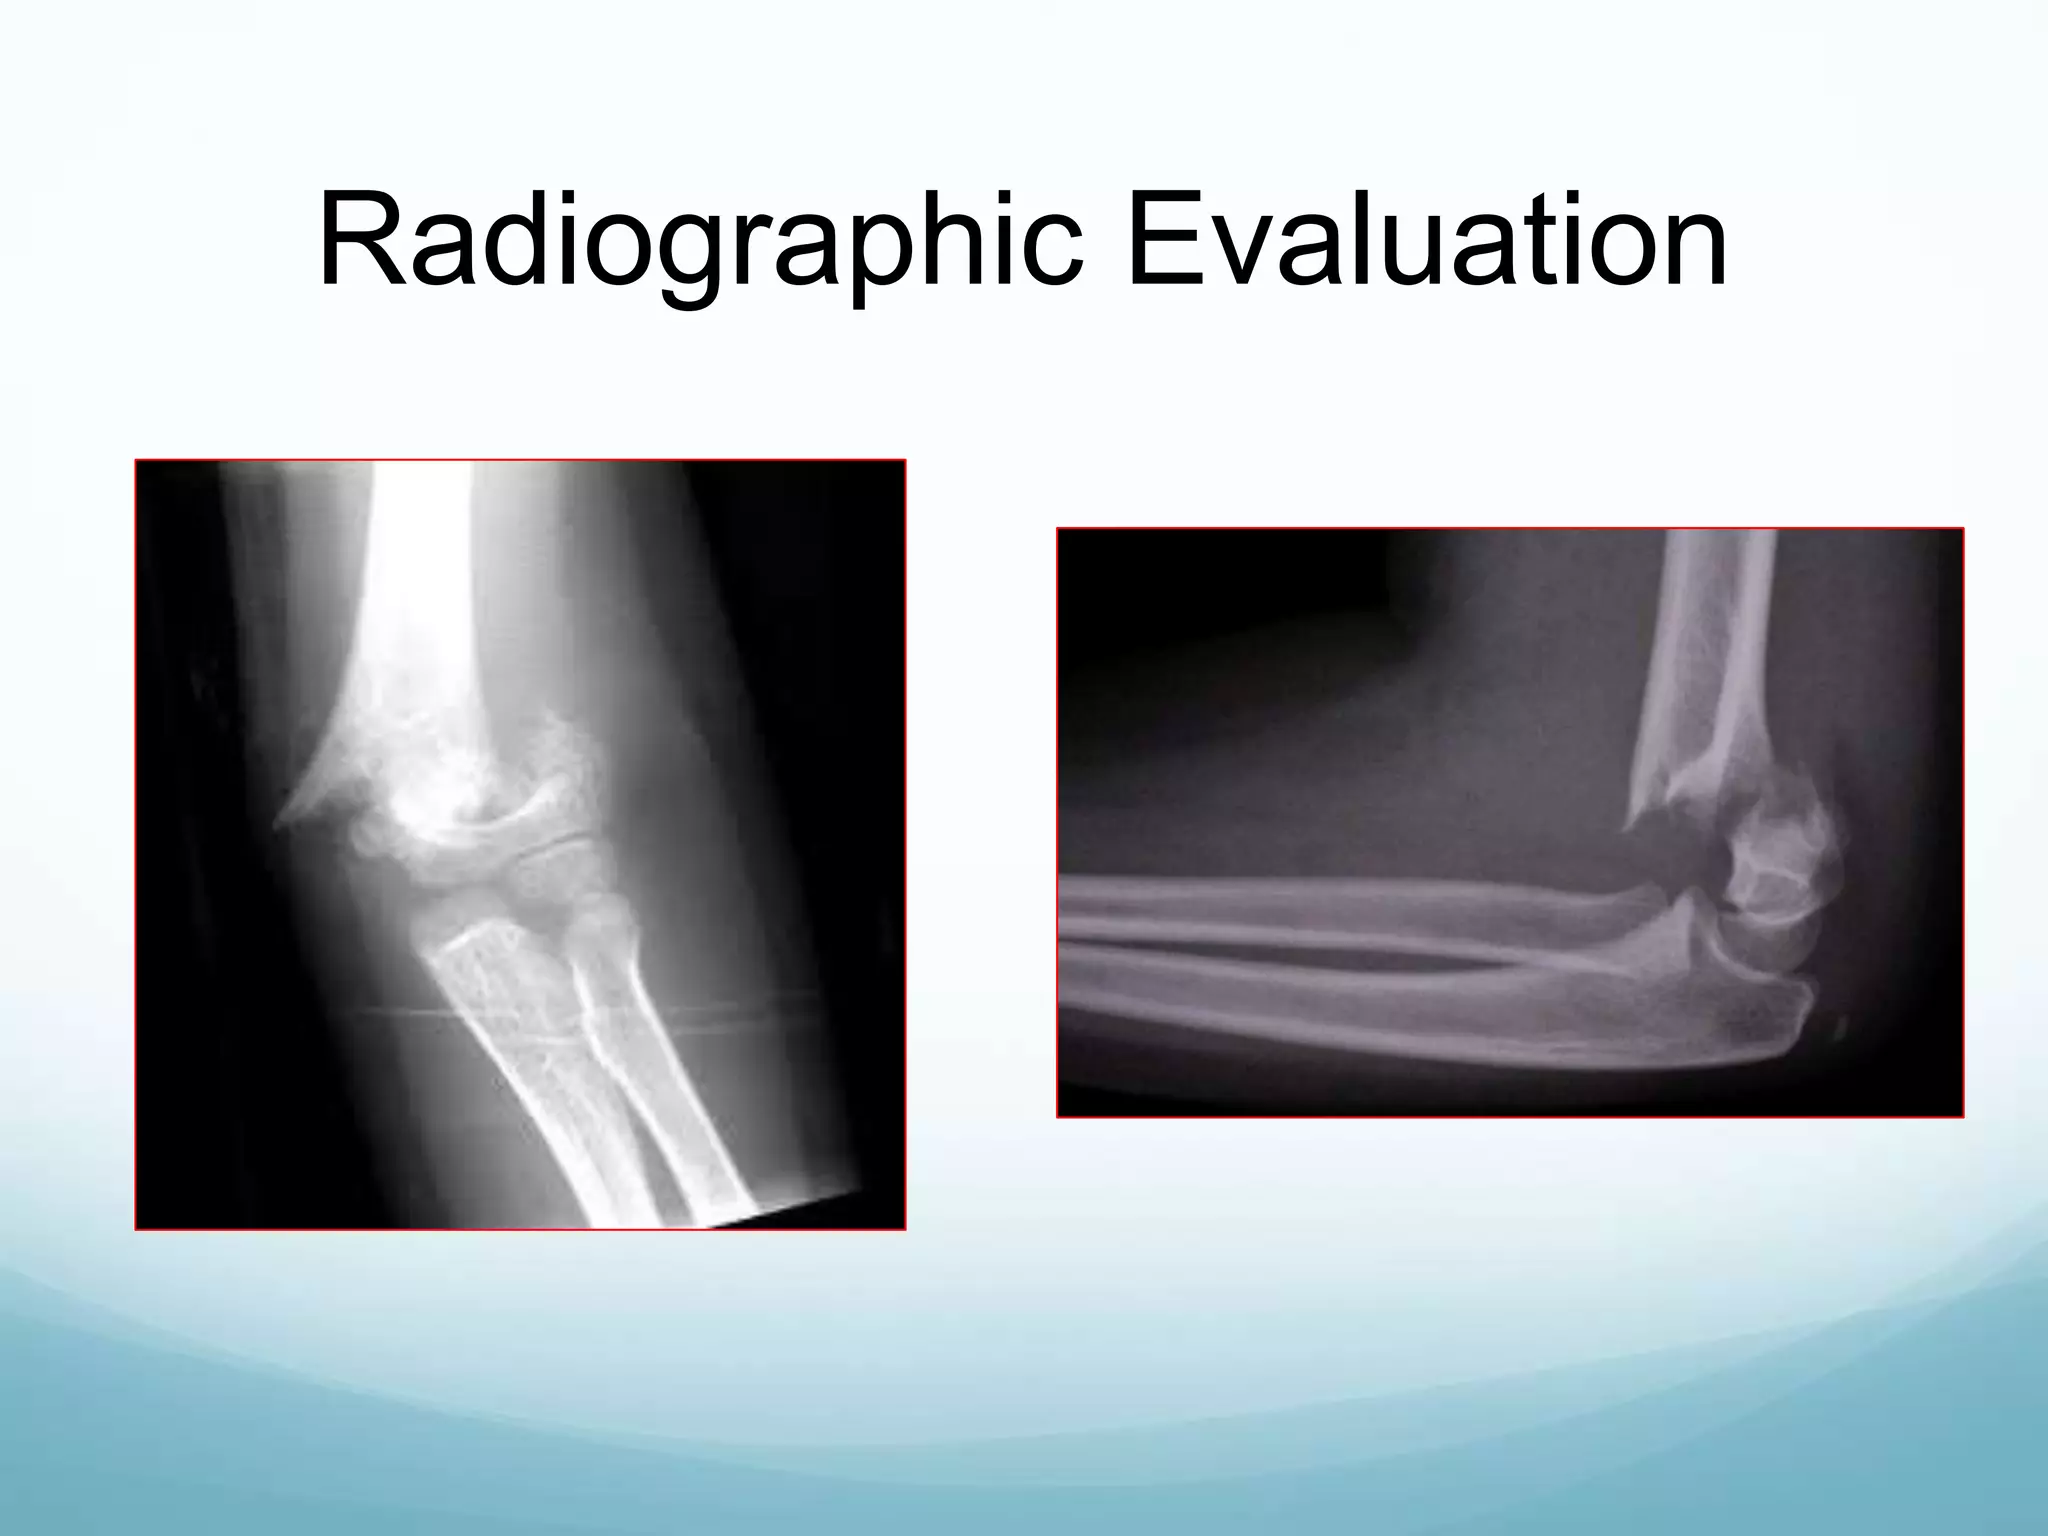

Radiographic Evaluation

Anterior humeral line Shaft-condylar angle

Fat pad

sign

Fish tail sign

Baumann’s angle:

Metaphyseal-Diaphyseal angle

Anterior humeral lineShaft-condylar angle Fat pad sign Fish tail sign